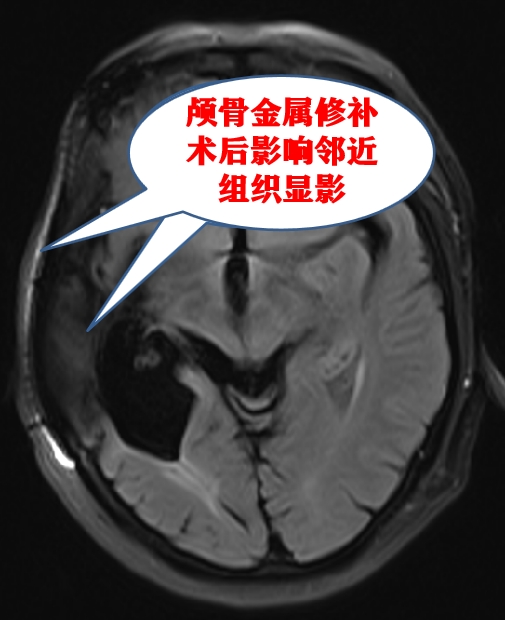

3.影响诊断。核磁共振检查依赖稳定均匀的磁场,获取被检查者体内各组织、器官等的含水量,从而形成清晰影像。如果有金属物质在检查部位的地方或者需要观察部位的附近,就会影响核磁共振的磁场从而导致伪影从而造成漏诊或误诊。

⑴骨科植入物(如钢板、钢针、螺钉以及各种人工关节等)及牙科植入物(如种植牙、固定的假牙和烤瓷牙等)可以由钢或钛合金材料组成,由于钢具有铁磁性,而钛合金具有非铁磁性,并且这些器材一般在手术时已牢固地固定在身体的相应部位,通常不会移动而导致伤害,但植入物可能会导致图像伪影或者发生热灼伤,因此需要工作人员进行评估后再决定是否进行检查。

⑶人工心脏瓣膜、瓣膜成形环以及颅脑修复板,这类的金属瓣架一般用不锈钢、钛、钴镍合金或其它超硬金属等制成,由于不同厂家产品的差异性,因此在核磁共振检查前需对材料进行评估确认后再进行检查。